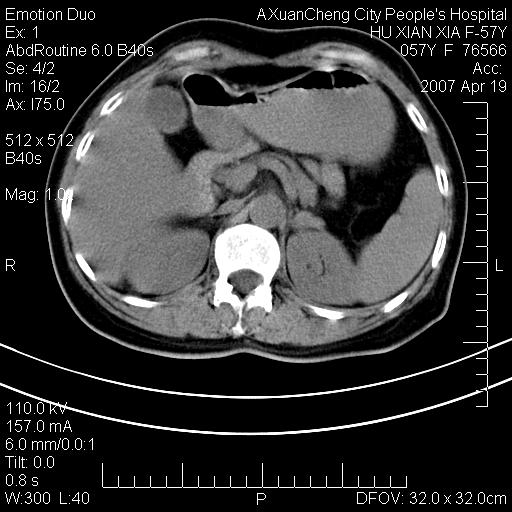

考虑:1、双侧肾上腺占位.2、肝左叶内侧段不规则低密度灶,建议强化扫描.

1.双侧肾上腺占位,转移首先考虑。

2.肝硬化,门静脉高压;肝左叶内侧段病灶建议增强。